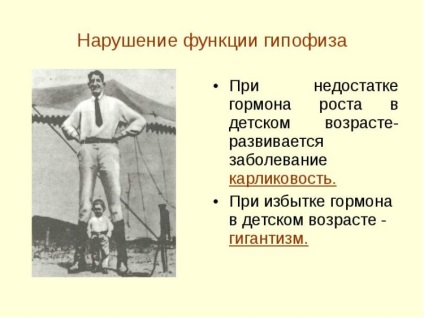

A legszembetűnőbb példa - a probléma a növekedési hormon (STH). Abban a felesleges korán jelent egy személyt gigantizmus. Ebben az állapotban a gyermek vagy serdülő túlságosan magas, de izomgyengeséggel, krónikus fáradtság szindróma, gyakran a látássérült és a testtartás. Ugyanez megsértése felnőttkorban provokáló akromegáliában - rendellenes növekedés a belső szerveket. arccsontok, valamint a lábak és kezek.

A növekedési hormon hiánya okoz törpeség. Struck ez az állapot a gyermek elkezd gyorsan lemarad társaik növekedés (átlagosan 10-15 cm). Felnőtt ilyen jogsértések elveszti súlyát és erejét szenved endokrin rendellenességek - padló és mások.